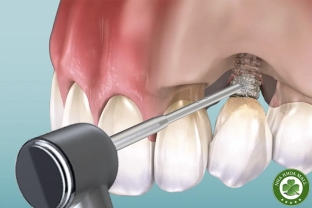

• Cấy ghép Implant: Công nghệ cấy ghép răng hiện đại, kỹ thuật nâng xoang, ghép xương.